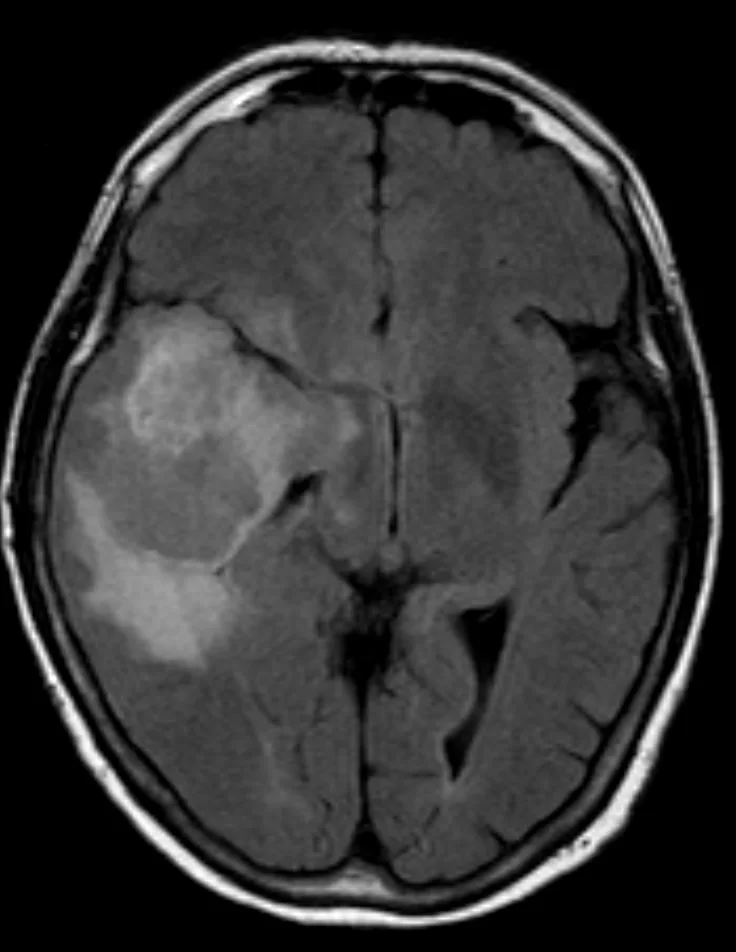

Η μαγνητική τομογραφία ανέδειξε ευμεγέθη χωροκατακτητική εξεργασία δεξιά κροταφικά με σημαντικό περιεστιακό οίδημα, ύποπτη για κακόηθες γλοίωμα.

Η μετεγχειρητική μαγνητική τομογραφία εγκεφάλου (substraction sequences) δείχνει πλήρη αφαίρεση της βλάβης. Η ιστολογική εξέταση ανέδειξε γλοιοβλάστωμα (IDH1/2 mutant, MGMT neg).